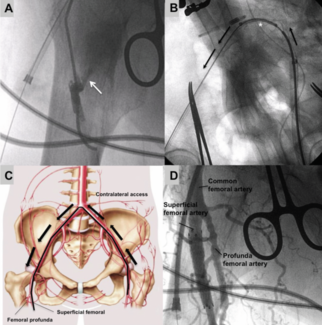

Leire Unzué, MD, PhD; Eulogio García, MD; Rodrigo Teijeiro, MD; Belen Rubio-Alonso, MD

Percutaneous AVF closure was performed post TAVI in a patient with severe aortic stenosis and an AVF between the right SFA and femoral vein.